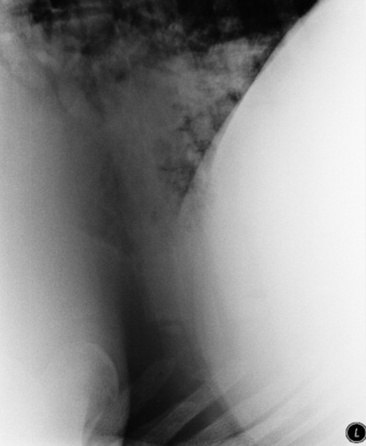

Thoracocentesis

image

Fig. 31-3 Thoracocentesis and therapeutic drainage in the horse. Pleural effusion can be large and bilateral. Samples should be obtained for culture and cytologic examination at the time the chest is drained.

Courtesy Dr. Corinne Sweeney, University of Pennsylvania, New Bolton Center, Kennett Square, Penn.